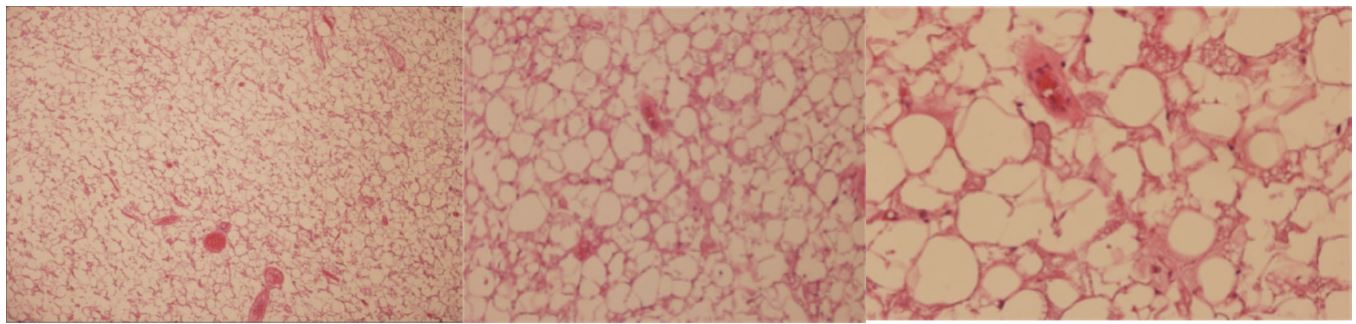

Figure 3: Histopathology section: A benign neoplasm, showing lobules composed of an admixture of palely staining uni vacuolated fat cells and eosinophilic multivacuolated hibernoma cells with a markedly enlarged cytoplasm filled with course vacuoles and eosinophilic granules.